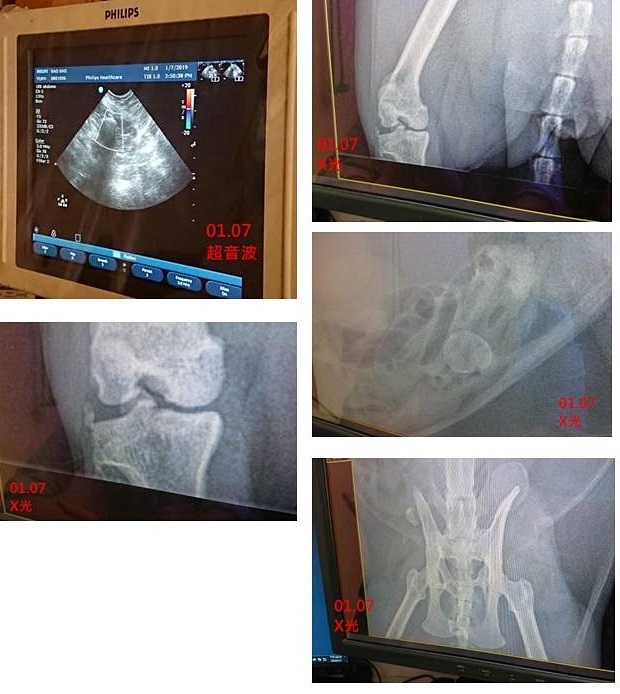

2019年1月工作人員發現抱抱尿尿行為異常,頻繁進出砂盆、久蹲尿少,立即約診沐恩醫院於1月7日進行檢查,醫師安排抱抱照X光,發現骨盆有舊傷跡象,有類似碎骨片物質,但因膀胱被骨頭遮住,無法確定是否有結石,先開口服止痛滴劑、抗生素、利尿通,並囑咐觀察、記錄尿量及持續回診追蹤;1月19日抱抱由泌尿專科武醫師看診,超音波檢查看到很多雜質但無結晶,先前服藥近兩週雖有改善但不夠理想,另因抱抱皮膚多處嚴重紅腫脫毛疑似黴菌,又有濃鼻涕,蘇璧伶醫師親自看診,安排抱抱進行血檢、皮膚及鼻涕採樣,做黴菌、細菌的培養,重新調整抱抱的用藥,使用另種抗生素及施打干擾素,因蘇醫師的病例中,干擾素對部份貓咪的鼻腔問題有顯著效果,希望抱抱也能得到治療效果。

從X光片上看起來,以前骨盆有受過傷,有一些像碎骨片的東西,沒有明顯結石的樣子,腎臟內沒看到有結石,膀胱有點太小,附近的微小白點,因仰躺照X光時,膀胱剛好被骨頭遮擋到,所以無法確定是否為膀胱的結石,另一個奇怪的影像是仰躺時,在偏左邊肚子的地方有異物,有可能是結石,但不在膀胱內,所以沒辦法很肯定是結石,需要照超音波再次確認。

以前骨盆明顯有受過傷,右腳比左腳長,有發炎退化的狀況,一是骨盆附近有碎骨片,因已是舊傷,如沒有造成疼痛或嚴重不適可不需擔心。

二是右腳膝蓋關節部位,有許多小突起,可能是關節發炎的舊傷,細微的白點,沒辦法確認是否是結石。

另一不明類似團塊物,在左腹腔內,是否有害還無法確認,超音波檢查,確認團塊是外圍有血流,內部沒有血流,還不確定是否為腫瘤,需要再觀察,此團塊位置不至於影響到排尿,需再追蹤是否變大或改變形狀等狀況。

X光不見得能顯示出所有結石種類,也有少數結石是無法成影在X光的,有一微小點點是否為結石還無法確定,超音波檢查因膀胱太小,醫師無法斷定,但至少尿道是沒有見到異物。

一、超音波檢查

超音波掃描時,有發現膀胱內一小顆白點,懷疑是血塊的物體,看來不像膀胱壁上的腫塊也不像是結石,暫時不用擔心,有可能只是超音波假影而已,週六再確認一下膀胱,還有沒有這血塊。